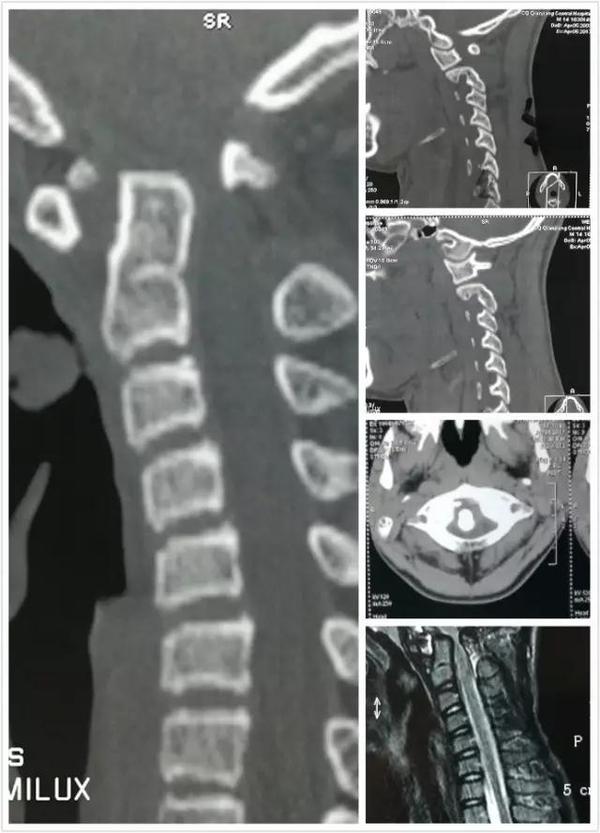

术前影像资料

术后影像资料

术前术后对比

2、术后复查见复位满意,脊髓减压充分,颈脊角纠正满意。

3、分析术前影像,本例为先天性颅颈畸形,外伤是导致其病情加重的诱因。理由:齿状突小骨和颈2椎体有皮质骨面;颈2变异,为先天性畸形证。